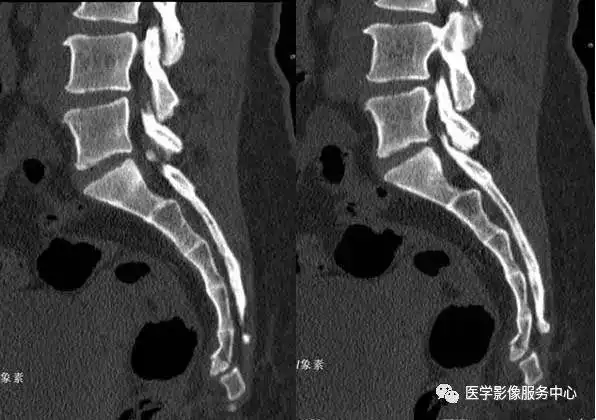

骶尾骨骨折易误诊为病变的3种假象,一旦遇到需警惕!